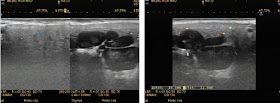

A 37 year-old with swelling of his left face.

Parotid gland on left side existed a cluster of lymph node-like, solid, echo poor, # 5-4-4mm in parotid gland and in subcutaneous layer.